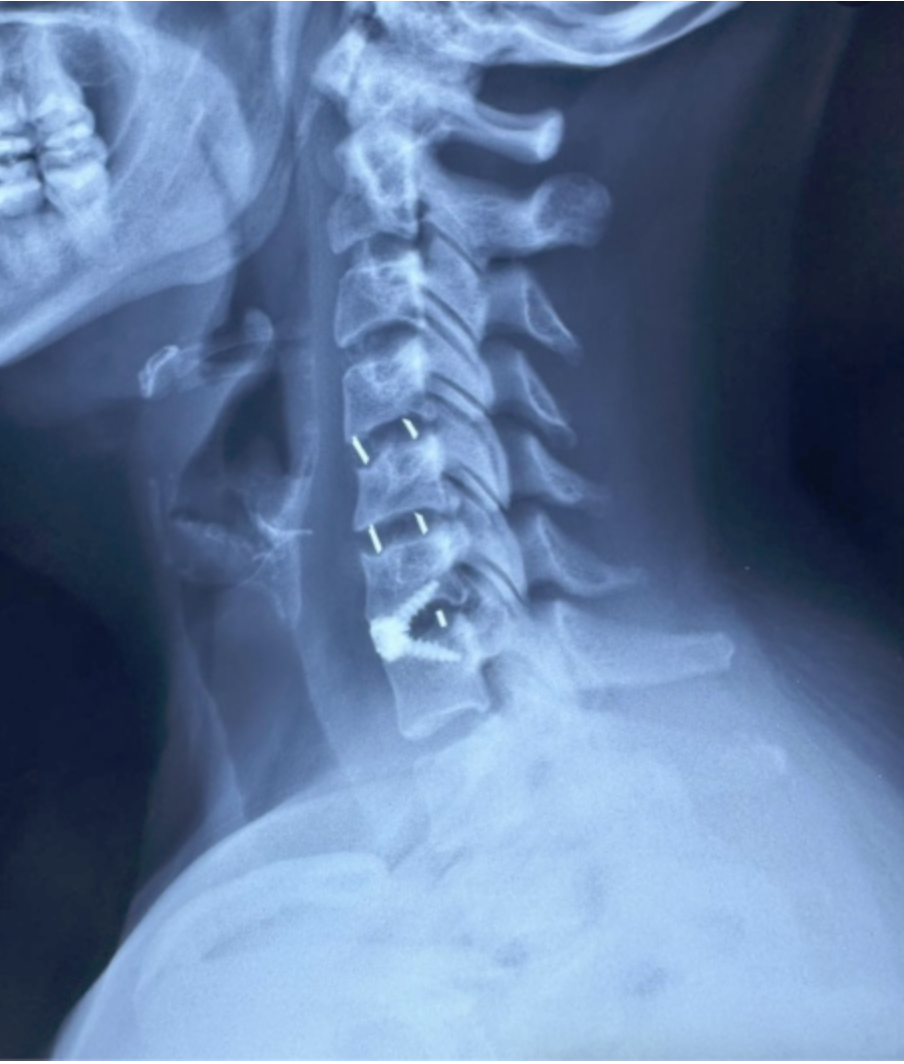

CIRUGIAS

RESULTADOS